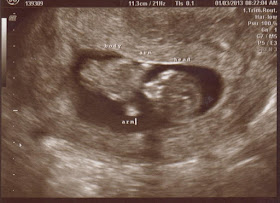

Ultrasound update

Good morning! Happy New Year everyone! This morning I had my ultrasound. I was expecting to see a little blob, a yolk sack and a faint heart beat. However, what I saw was much different. I saw a baby! With arms and a strong heart beat. If everything went as planned with the fertility meds I would be about 7-8 weeks right now. BUT apparently I became pregnant BEFORE I started taking the fertility meds. Which would probably explain the lack of period after the provera as well as the constant positive ovulation test. The quick positive on the pregnancy test also explains that I was pregnant before the provera. I am completely confused as to when I would have gotten pregnant. I mean with the given dates, it was around Halloween but I have not had a period since I lost the twins. I will upload pictures of the ultrasound a little later. As of right now I am measuring at 12 weeks with a due date of July 25, FOUR days after Owen's!!! I feel bad they are so close but it is still exciting!